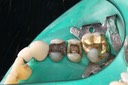

Larry Fujioka #12-12 prep